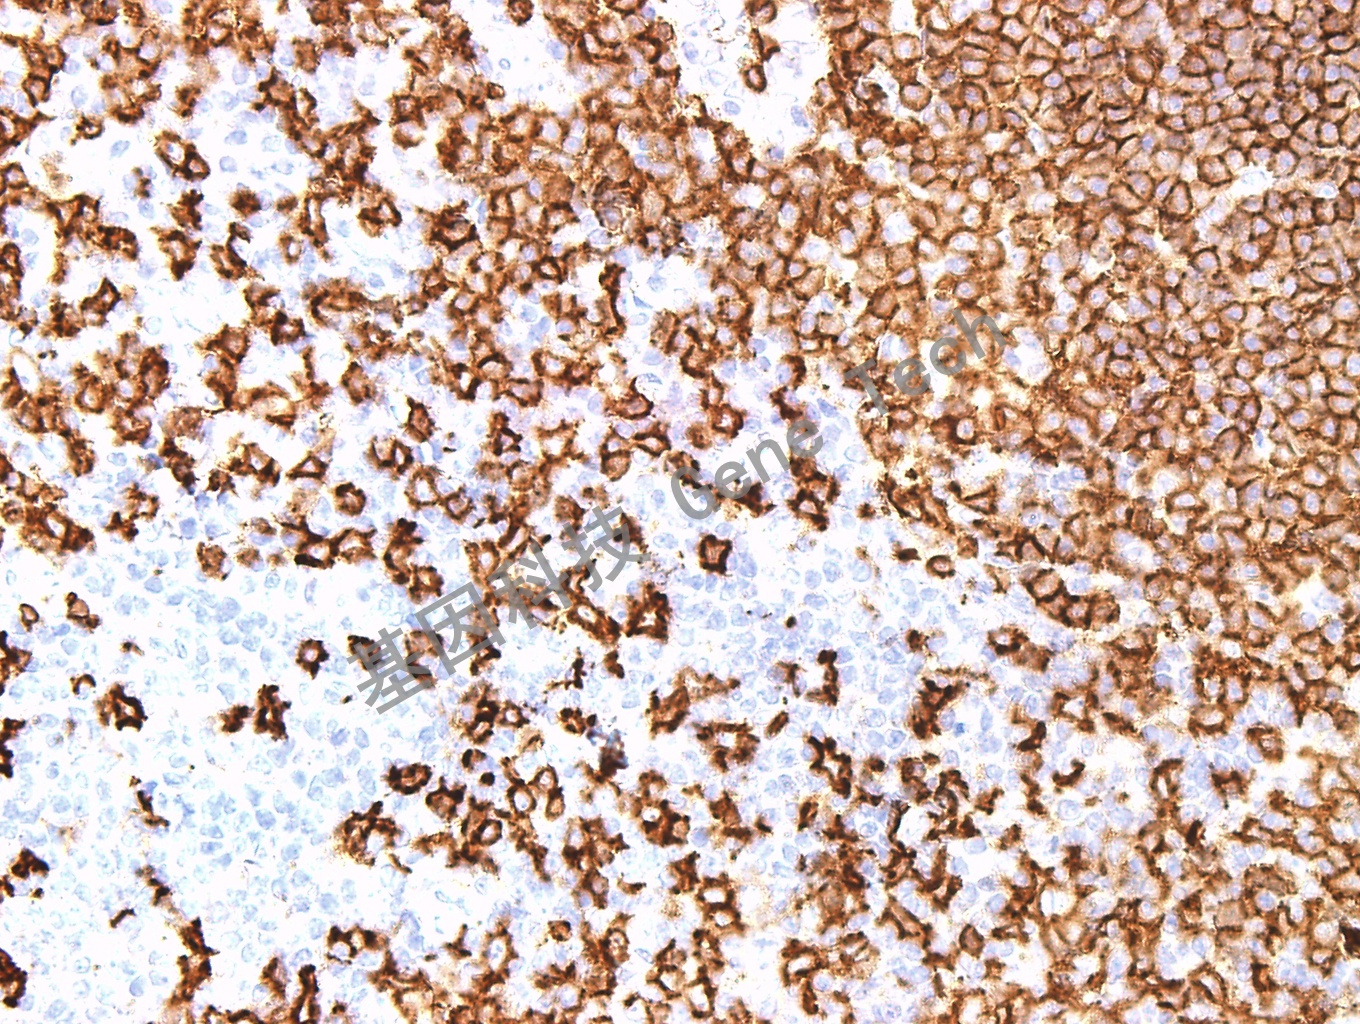

扁桃体石蜡切片,用 CD20(GM0755)染色,细胞膜阳性,DAB 显色。(40×)